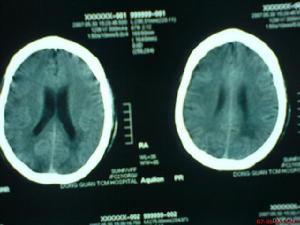

主要表現為頭痛、嘔吐、視乳頭水腫、癱瘓、部分性運動性癲癇發作等,常伴不同程度的意識障礙。這些雖然擬似顱內占位病變的症狀,但起病急,病情迅速加重,從起病至症狀頂點短者僅數小時,多數均在一個月內;顱內壓急劇增高,部分患者可迅速出現顱內壓增高危象;頭顱CT和MRI檢查均可見彌散性腦水腫和腦軟化區等,均有助與腦瘤鑑別,但確診有時需依賴開顱探查或立體定向鑽孔穿刺進行腦組織活檢。

4、顱腦CT可見腦內大小不等、邊界不清的低密度灶。

5、放射學檢查:常規頭顱放射學檢查對散發性腦炎的診斷無重要價值。頭顱CT有時可見大腦半球多個散在的軟化灶,對排除占位性病變有一定意義。